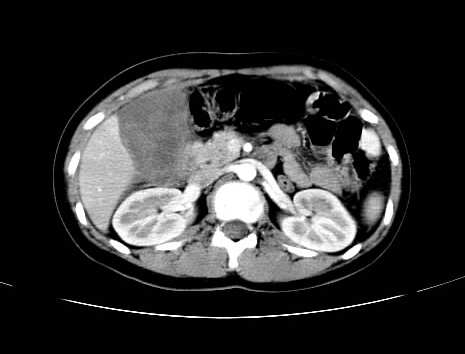

女 16岁  右上腹痛一天,无其他不适

肿块最大径位于十二指肠降段与水平段移行处,并且与肝脏压迹呈“0”形征,可以考虑位于肝外并与胃肠道关系紧密,考虑胃肠道间质瘤(gist)可能较大,须除外神经节起源肿瘤。

肿块与十二指肠关系密切,支持间质瘤诊断.肝脏与结肠均为受压改变.

右下腹巨大肿快,密度不均匀,内见坏死低密度区,边界清楚,与周边胀器明显有分界,未见强化,多考虑来源于间叶组织的良性肿物.

病灶巨大,少部分向肠腔内生长,大部分向长腔外生长。其密度不均匀,增强显示明显不均匀强化,并见有大片状始终不强化的不规则坏死液化区。虽然病灶中上部形态尚可,病人又如此年轻,但中下部形态、密度、强化特点强烈提示为恶性病灶。综上,我考虑本病例为:恶性胃肠道间质瘤。